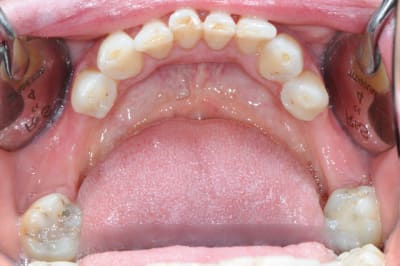

CAS 1

demande de restauration avec implant, mais, ne veut pas entendre parler de greffes et greffons.

la ROG lui semble plus "naturel".

photos

1-2-3 situation de départ